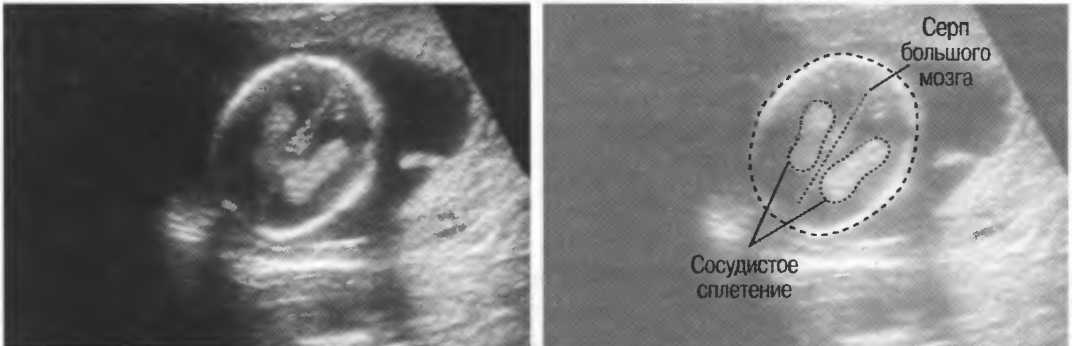

Кисты на узи у плода

Кисты на узи у плода 114 фото